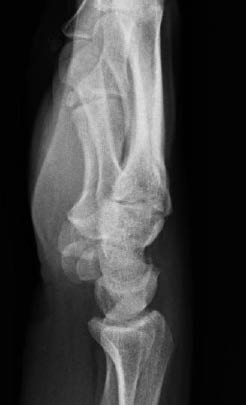

The diagnostic imaging includes standard PA and lateral radiographs. When reviewing these plain radiographs, one should pay close attention to the space between the individual carpal bones on the PA view. The space between the bones should be uniform. The presence of a gap greater than 2 mm is indicative of ligamentous injury and possible carpal instability.32 Gilula described radiographic lines for discovering carpal bone injuries due to ligamentous and bony injuries of the wrist.33 In an uninjured wrist, the articular surfaces of the proximal and distal carpal rows form smooth arcs at the radiocarpal and midcarpal articulations.32 (See Figure 6.) A disruption of any of these lines is indicative of carpal instability or possible injury.32 The lateral view of the wrist is often the best view to appreciate a perilunate dislocation. Remember the "3 Cs" sign when examining a lateral radiograph of the wrist. The "3 Cs" are formed by the articulations of the distal radius, lunate, capitate, and base of the third metacarpal, respectively. (See Figures 7 and 8.) The arrangement of the 3 Cs in a perilunate dislocation is disrupted at the level of the capitate, which represents the third C. It is displaced dorsally toward the lunate, which remains in contact with the radius.12 (See Figure 9.)

Figure 7: Normal Wrist Lateral Radiograph

Figure 8: Relationship Between the Distal Radius Surface, Lunate, and Capitate on the Lateral View

Figure 9: Perilunate Dislocation with Dorsal Displacement of the Capitate